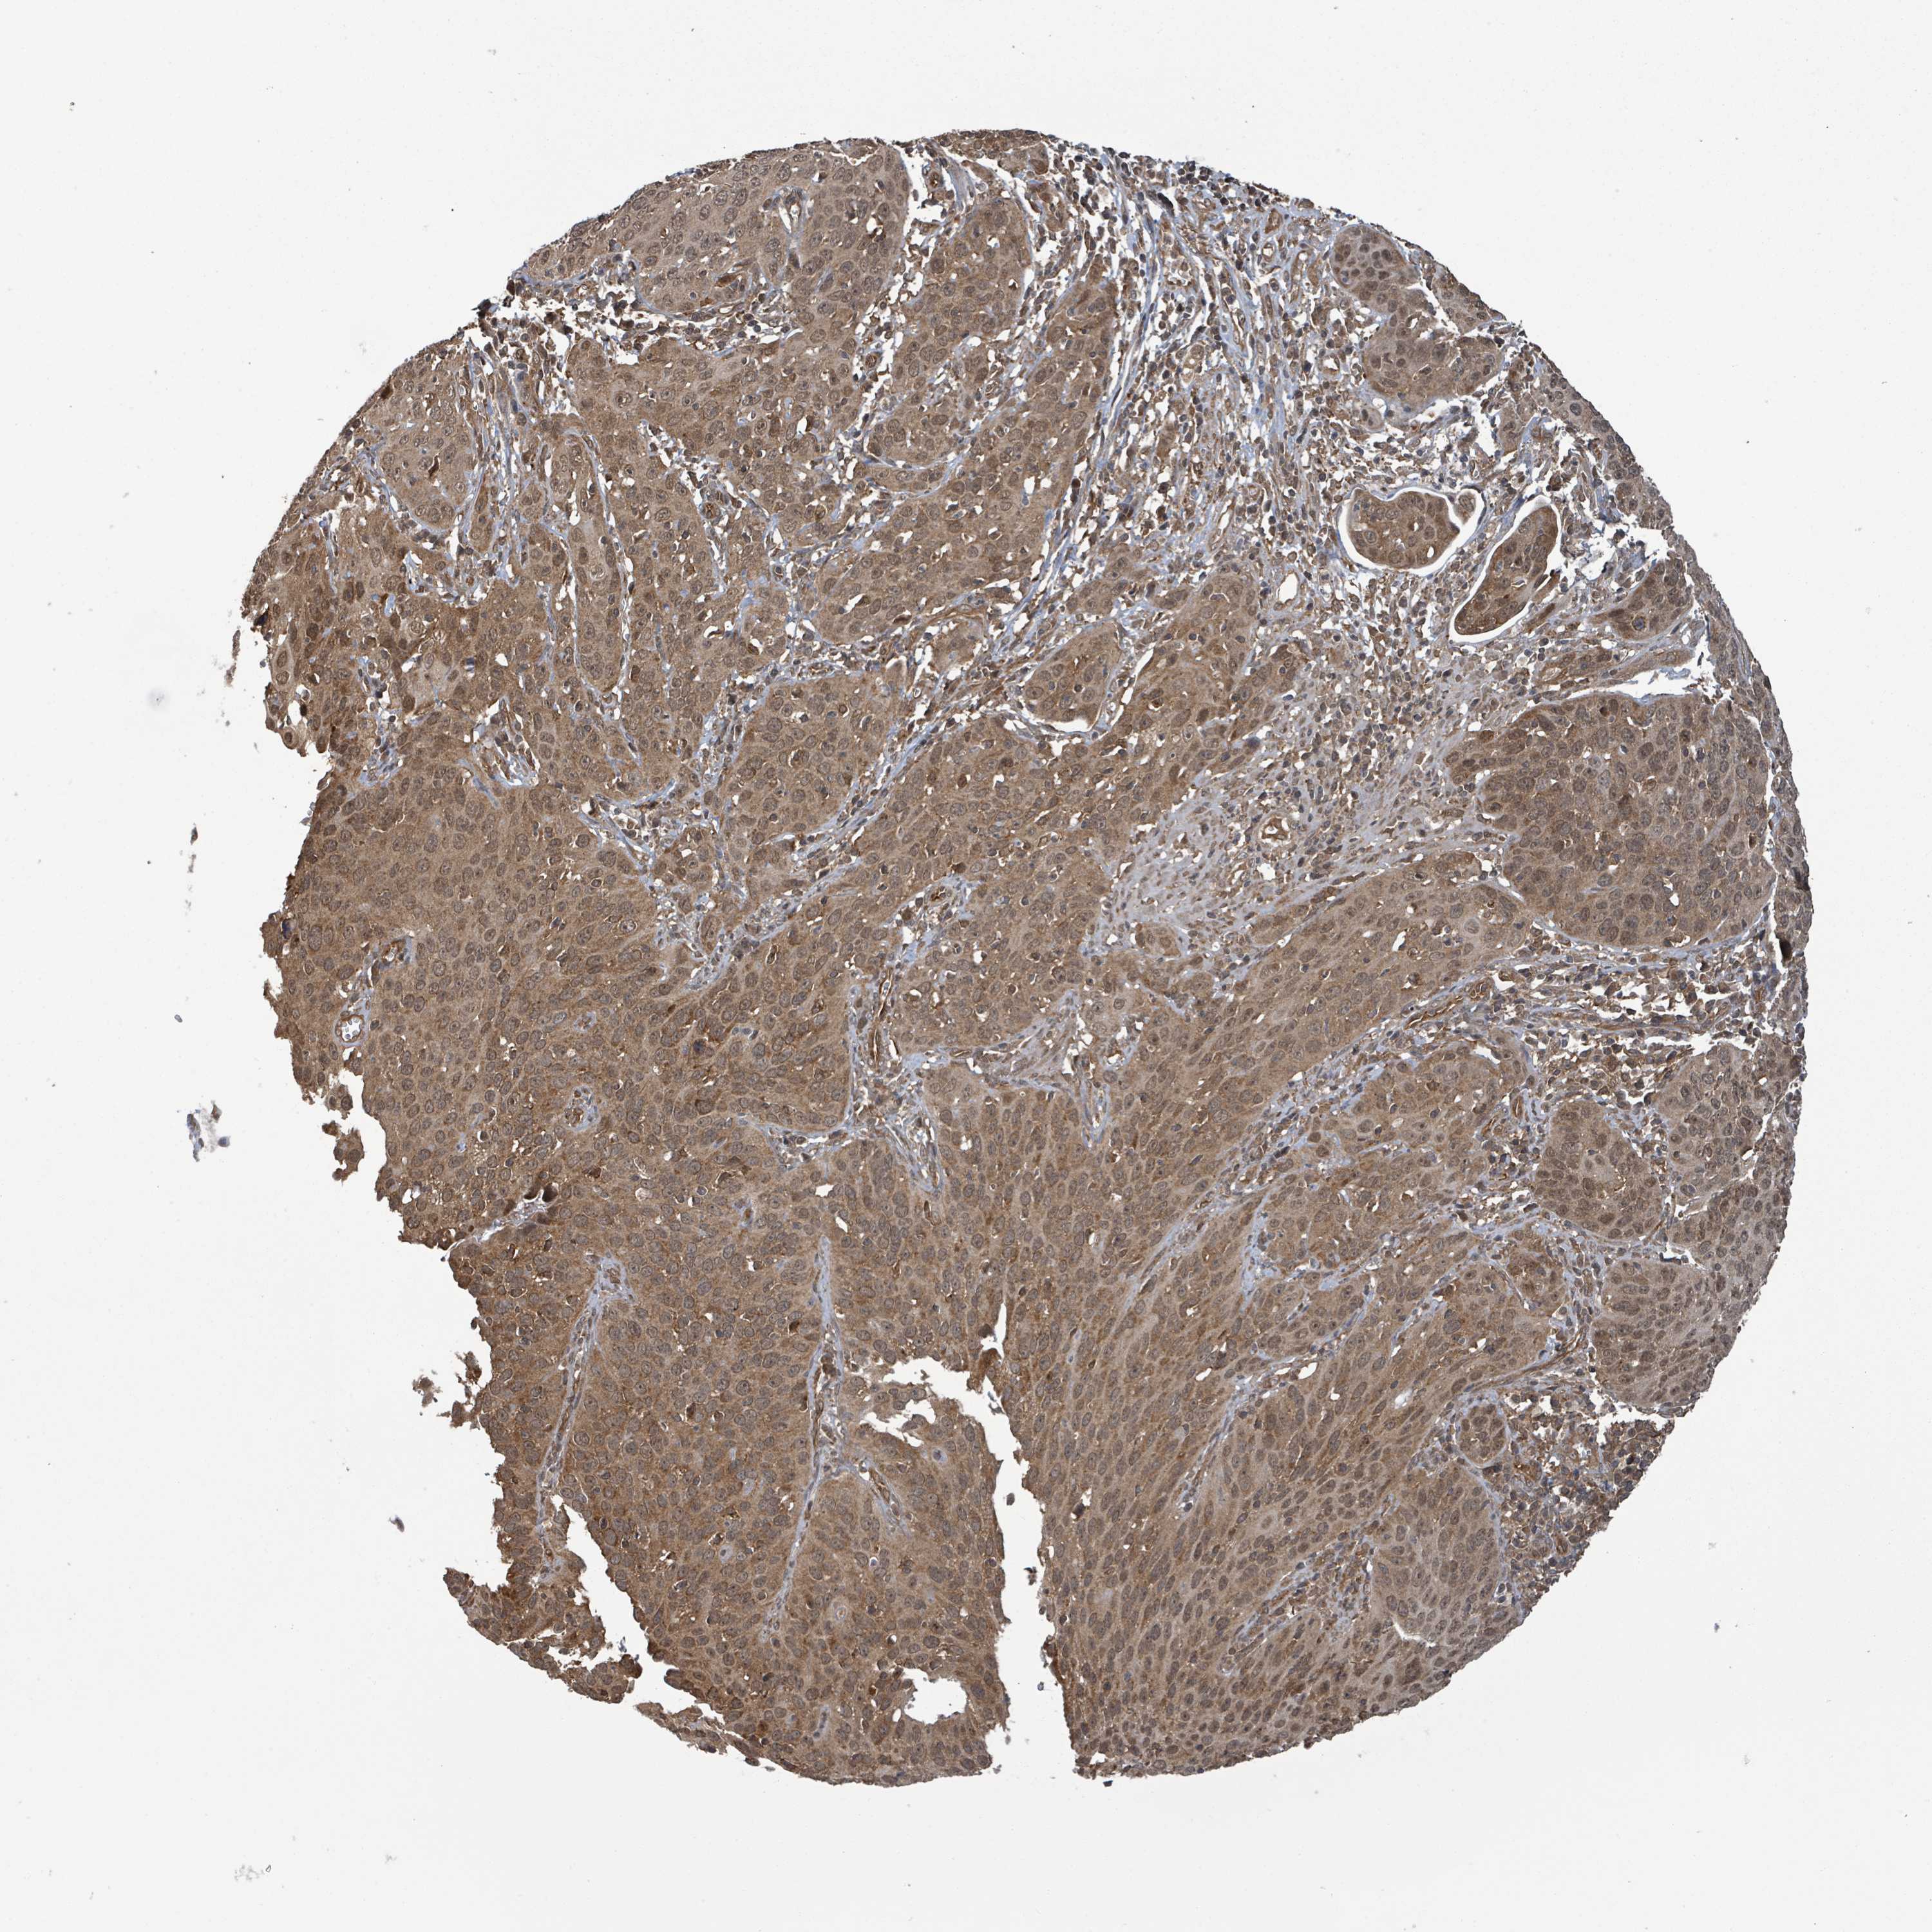

CERVICAL CANCER - Protein expressioni

A mouse-over function shows sample information and annotation data. Click on an image to view it in a full screen mode. Samples can be filtered based on level of antibody staining by selecting one or several of the following categories: high, medium, low and not detected. The assay and annotation is described here.

Note that samples used for immunohistochemistry by the Human Protein Atlas do not correspond to samples in the TCGA dataset.

Antibody stainingi

Antibody staining in the annotated cell types in the current human tissue is reported as not detected, low, medium, or high, based on conventional immunohistochemistry profiling in selected tissues. This score is based on the combination of the staining intensity and fraction of stained cells.

Each image is clickable and will lead to virtual microscopy that enables deeper exploration of all samples and also displays staining intensity scores, fraction scores and subcellular localization as well as patient and tissue information for each sample.

Antibody HPA052450

Squamous cell carcinoma, NOS

Adenocarcinoma, NOS